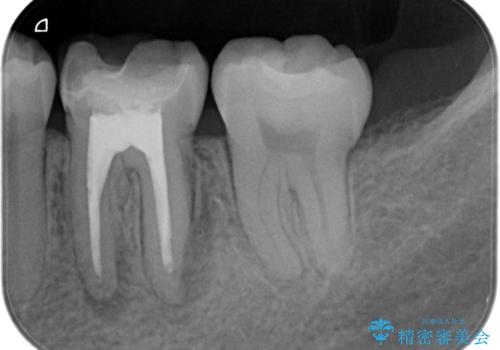

- 昔他院で根管治療を行った歯の病気が再発したことを主訴に来院されました。

レントゲンにて根尖に病変を認め、根尖性歯周炎の診断のもと以下の治療をご提案しました。

1、再根管治療を行い、3ヶ月以上経過を待ち、治癒しなければ外科的歯内療法を行う。

2、外科的歯内療法を行う。

以前の根管治療の質が不明なこと、補綴処置のやりかえにメリットがあることから、1の選択肢をお勧めしましたが、費用対効果の面を患者様と相談し今回は外科的歯内療法で治療することとしました。